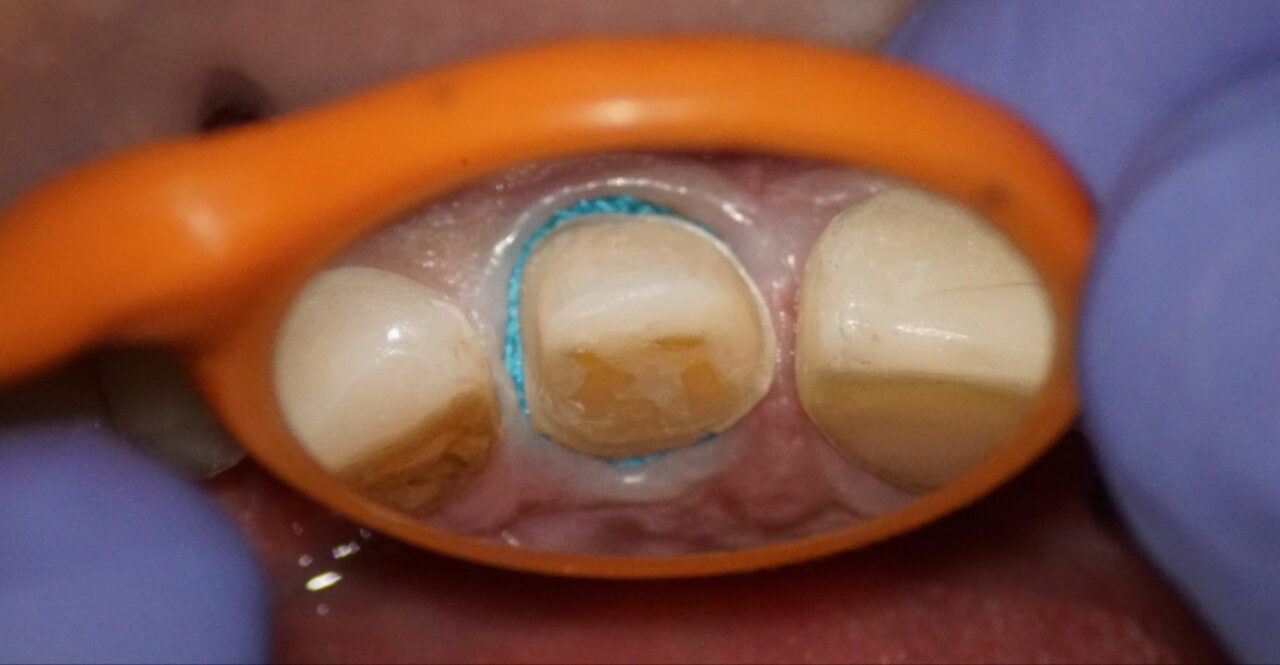

麻酔をした後にラバーダム防湿をして、随腔内を明示した写真です。